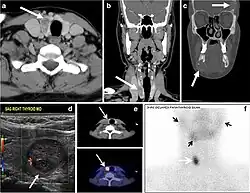

Parathyroid adenoma (PA) is the most common cause of primary hyperparathyroidism. Ectopic parathyroid adenoma is rare. The third and fourth pharyngeal pouches represent the embryological origin of the parathyroid tissues, and ectopic parathyroid adenoma can ultimately develop anywhere along their migration course. In a large retrospective study of patients with primary hyperparathyroidism, PA was detected in the intra-thyroid location in 0.7% of cases. In another retrospective analysis of 202 patients with ectopic PA, the intra-thyroidal location was found in 18% of the cases. Intra-thyroid parathyroid adenomas mimic thyroid nodules in CT scans and may even show uptake on a thyroid iodine scan. Correlation with laboratory workup, including measurement of serum parathyroid hormone and calcium level, is required. In addition, the evaluating radiologist should search for radiological manifestations of hyperparathyroidism, such as osteopenia, bone resorption, and brown tumours (Fig. 22).[1]

Fig. 22. A 26-year-old male patient with elevated serum parathyroid hormones and calcium secondary to intra-thyroid parathyroid adenoma. a, b Enhanced axial and coronal CT scan of the neck demonstrate a well-defined hypodense right thyroid nodule (white arrows). c Bone window coronal CT scan shows lytic expansile lesions at the right mandible and left frontal bone (white arrows). d Transverse colour Doppler ultrasound of the neck demonstrates a well-defined, heterogonous, predominantly hypoechoic right thyroid nodule measuring 2.7 cm, with mild increased vascularity and no internal micro-calcifications (white arrow). e, f Delayed anterior planar and fused SPECT/CT parathyroid Sestamibi scan at 2 hours demonstrate persistent focal activity in the right thyroid lobe (white arrows). Note the scattered mandibular/maxillary uptakes in planar image representing the known brown tumours.[1]

In the case of inconclusive Tc99m Sestamibi and neck US imaging, FNA biopsy with FNA-iPTH (intact parathyroid hormone) measurement can provide simultaneous biochemical and cytological evidence. Elevated FNA-iPTH measurement, as compared to serum iPTH, is considered positive and diagnostic of parathyroid adenoma.[1]